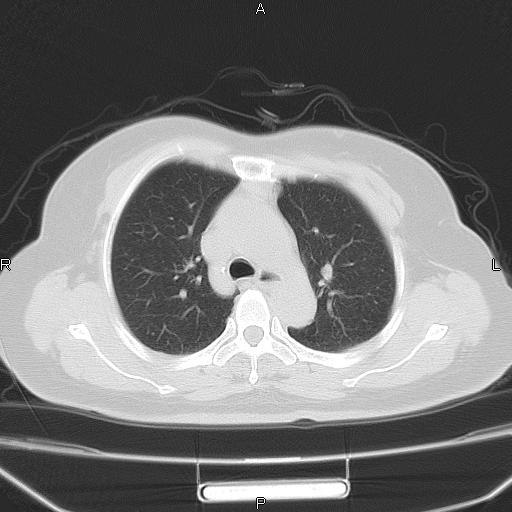

胸腺瘤

女、63Y 双眼睑下垂,早轻晚重。 胸腺瘤???

结果胸腺瘤